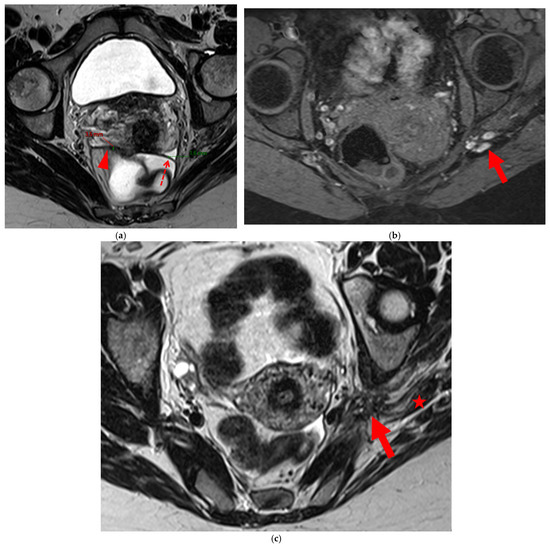

Figure 7. Pelvic MRI scans of two patients with HTD type 5B USLs. (a) Patient 1: sagittal T2WI shows a microcystic nodule (arrow) within the origin of the right USL (arrowhead). (b,c) Patient 2: axial (b) and sagittal (c) T2WI show a nodular left USL with spiculated margins (arrow) and a right ovarian endometrioma (arrowhead).

A type 5B USL (Figure 7) is nodular with spiculated margins. A type 5B USL may also display an isolated nodule with microcystic content.